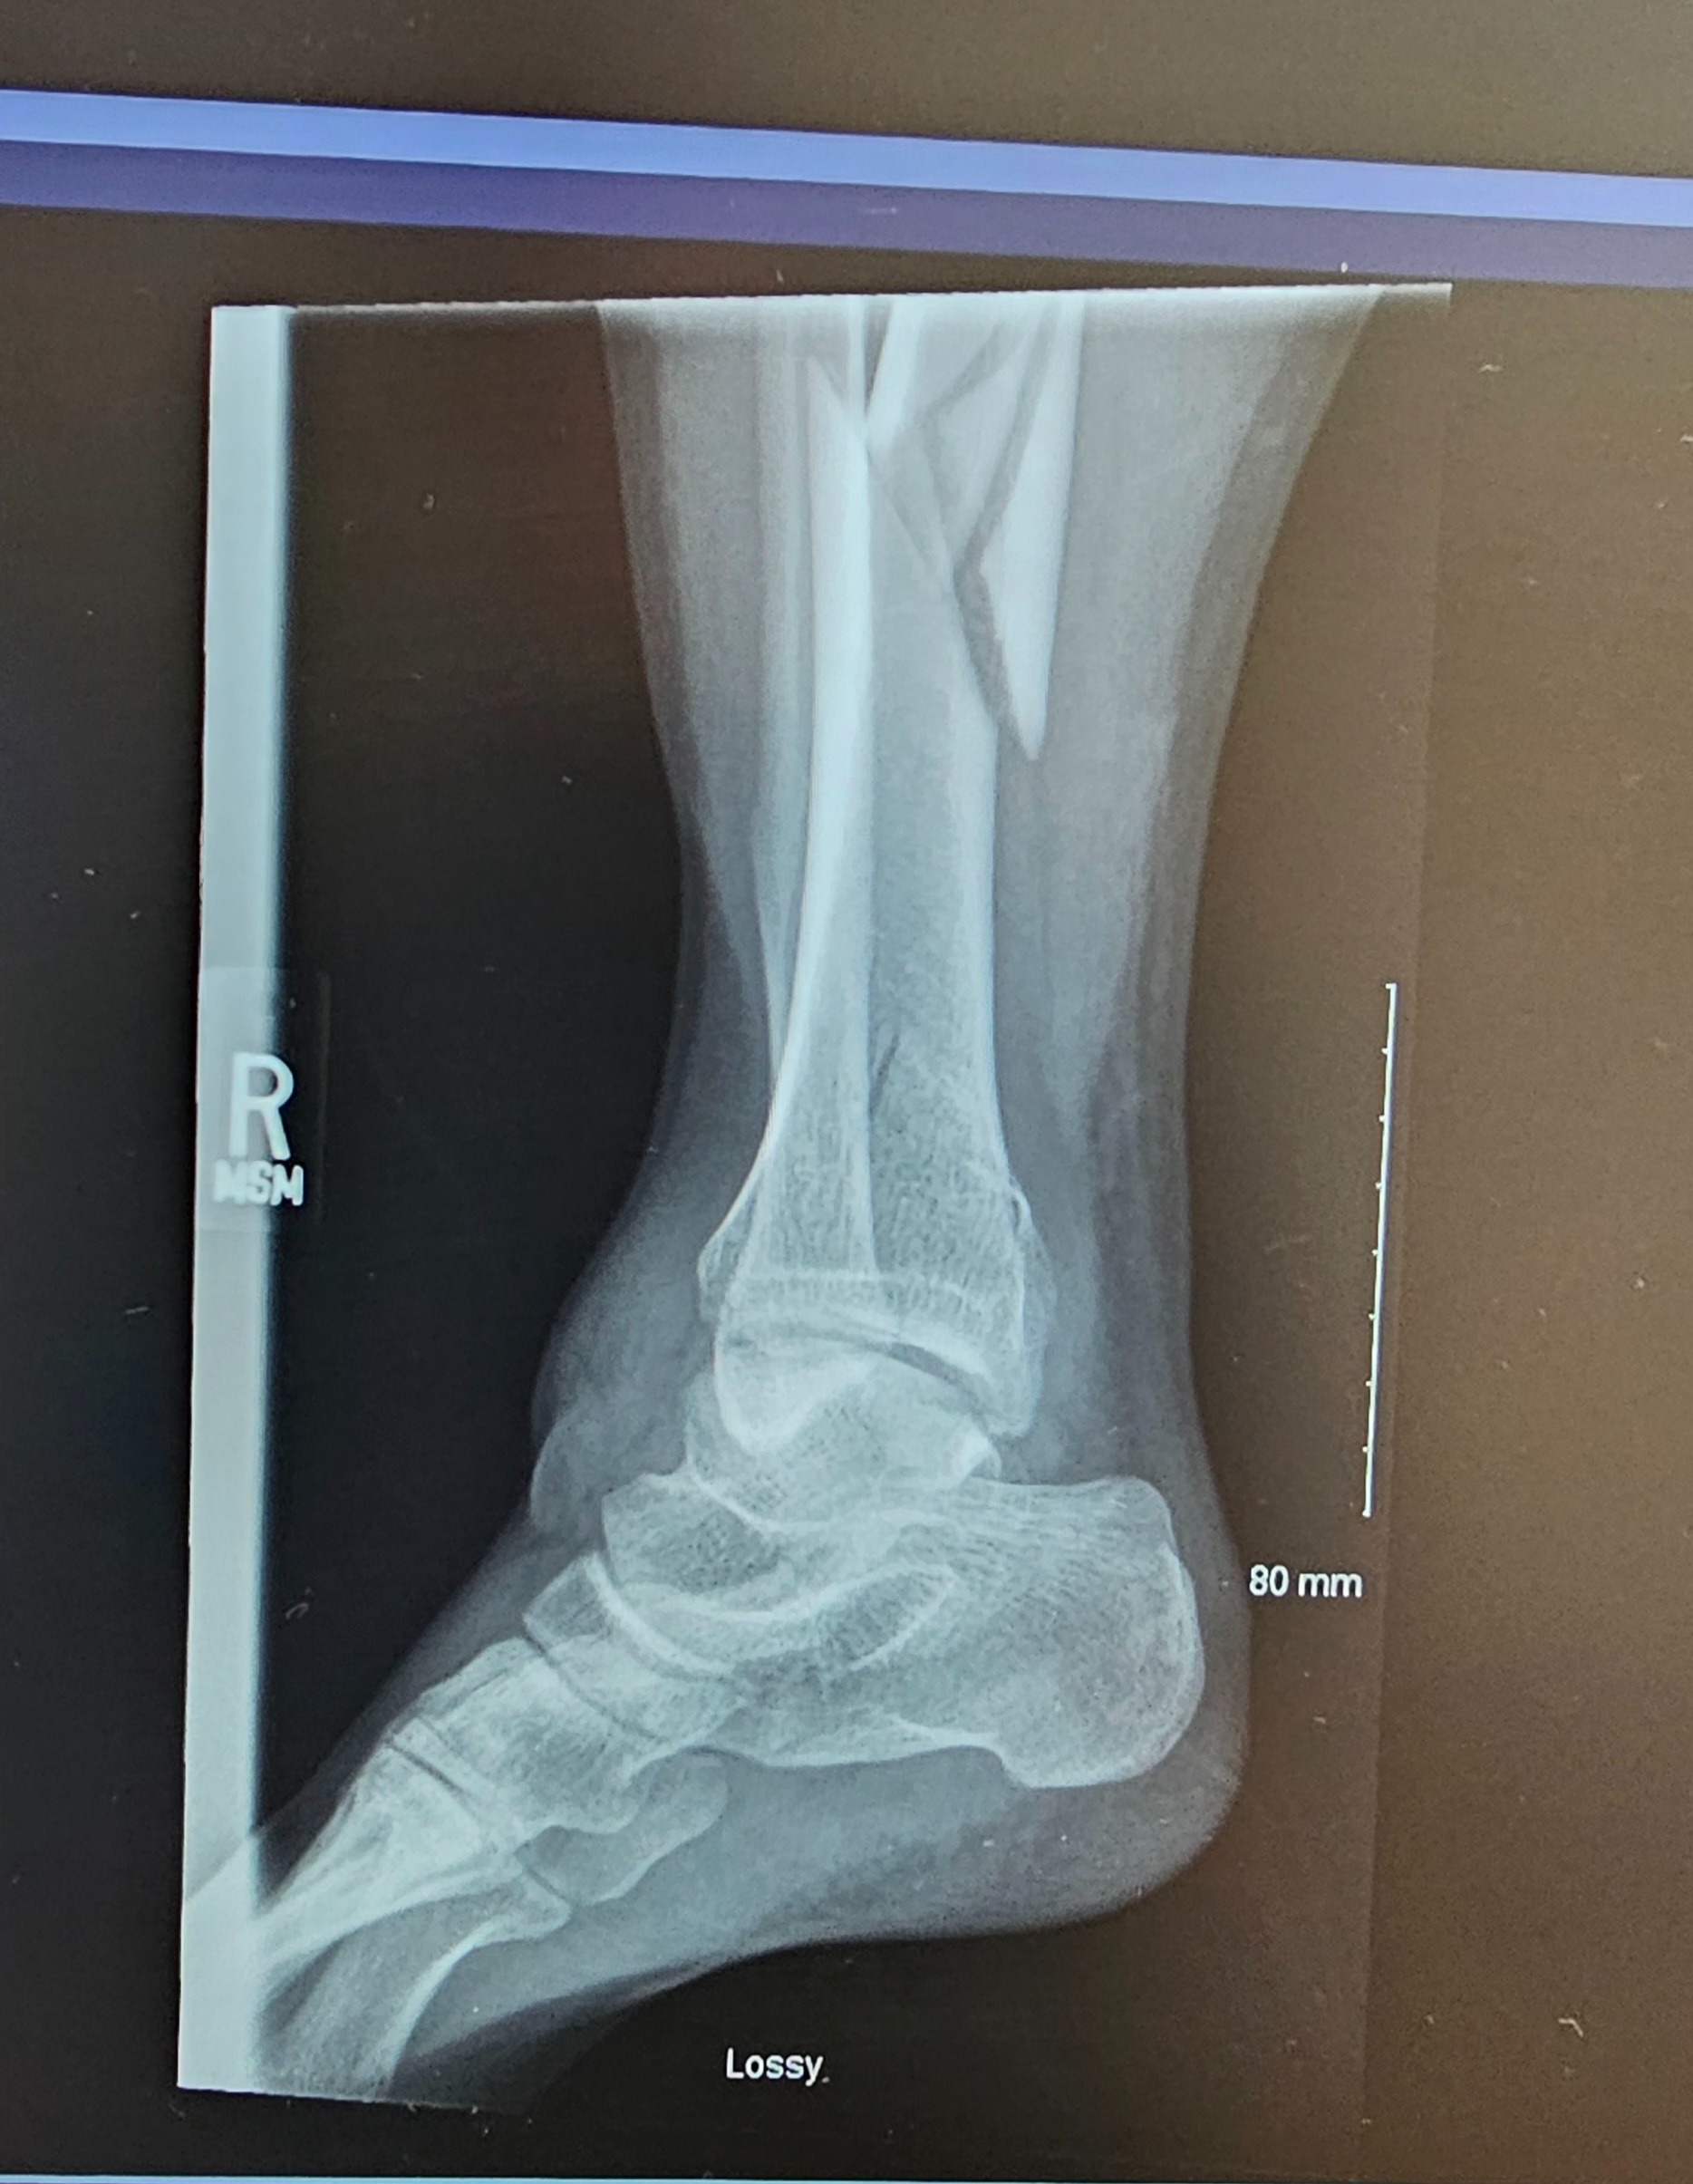

I’ve now been in the hospital for a week, recovering from surgery for a broken tibia, fibula, and ankle. The doctors say I can’t put any pressure on my leg or foot for at least eight weeks. I don’t have health insurance or any job benefits, and my bills are piling up—rent, car payments, and daily expenses. I’ve worked in landscaping for eight years, and it’s devastating to think I could lose everything I’ve worked for. I never thought I’d be in a position to ask for help, but I’m facing the possibility of losing my home and everything I’ve built. I’m doing everything I can to get assistance, but it’s not easy, and I’m running out of options.